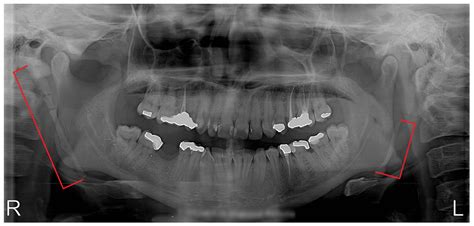

Diagnosing this condition requires more than just a physical examination of the throat. Because the root cause is structural, medical imaging is necessary to confirm the elongation of the styloid process or the calcification of the stylohyoid ligament.

• Computed Tomography (CT) Scan: This is the gold standard for diagnosis. A 3D CT scan of the neck clearly reveals the length, angulation, and thickness of the styloid process.